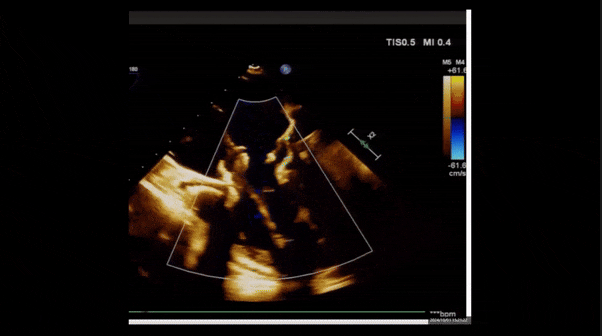

術前TEE評估

1、3D TEE顯示雙房及右室擴大,右室中段直徑40mm,右室FCA 52%。三尖瓣環TAPSE 22mm,三尖瓣環左右徑49mm,三尖瓣隔葉長度16mm,前葉長度21mm,后葉長度34mm,三尖瓣前隔gap 11mm,后隔gap 5.6mm,AP gap 12mm,診斷極重度功能性三尖瓣返流(Type I型三尖瓣:Torrential FTR 5+)。

2、彩色多普勒顯示:收縮期三尖瓣口返流束起源于后隔交界、前后葉之間及前隔交界,返流束縮流頸最大寬度27mm,三尖瓣返流口EOA=2.02cm2,返流容積124ml,收縮期三尖瓣返流峰值速度2.64m/s,返流峰值壓差28mmHg,PAPs 43mmHg,舒張期三尖瓣口平均跨瓣壓差1mmHg,肝左靜脈可見明顯逆向血流波。